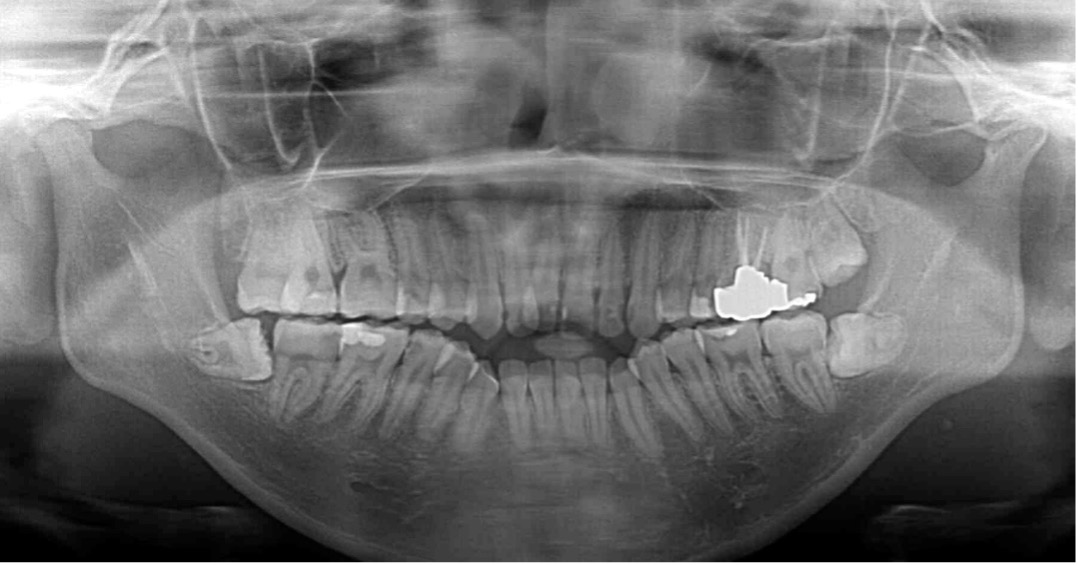

パノラマX線写真で抜歯すべき親知らずを確認

上下左右に 第三大臼歯(親知らず)が4本あることがわかります。今回の治療ではこれをすべて抜歯しました。

開咬の症例で親知らずがある場合は抜歯することが多いです。

なぜ抜歯するのかには所説あるのですが、親知らずが1つ前の歯を垂直的に押す力が加わると、奥歯の咬み合わせが高くなってしまい、開咬が悪化する場合があるからと言われています。